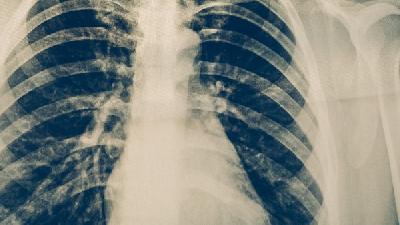

什么是小细胞肺癌